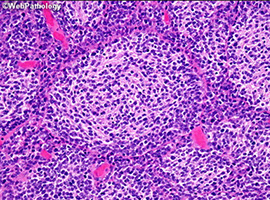

Pineocytoma

Rare tumor MC in adults

Imaging: Homogenously contrast enhancing; can be solid or cystic

Micro: sheets of small, monotonous cells that look like normal pineocytes

- large "pineocytomatous" rosettes are often seen; no/few mits; can see degenerative atypia in benign tumors

- synaptophysin and neurofilament (+)